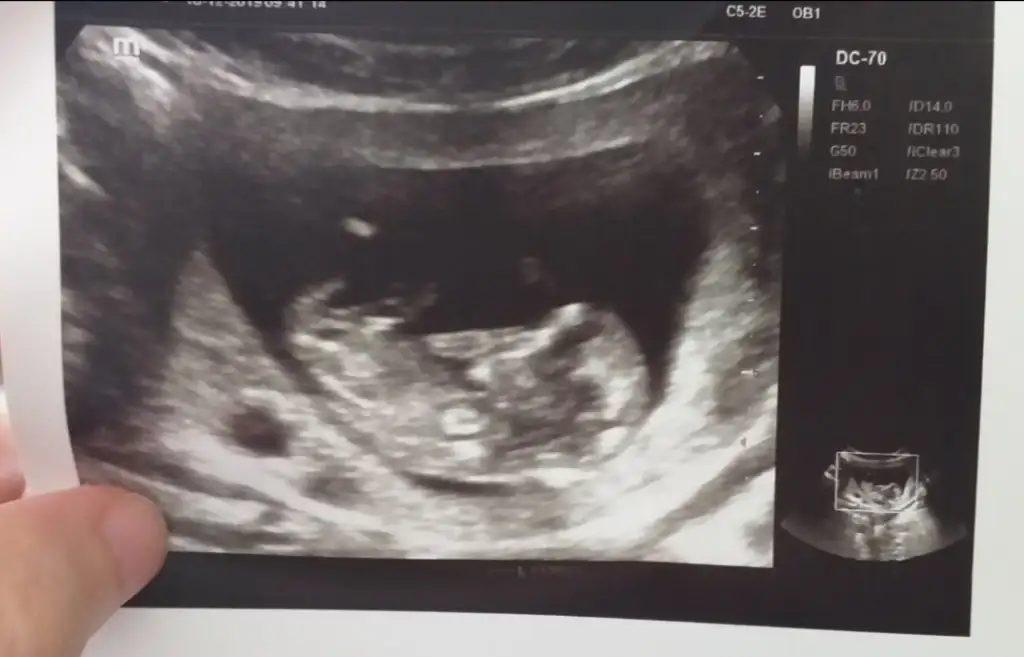

Buna göre kız sanki ama 11 +yada 12+ usg de paylaşın değişebilir nubu bu haftalarda iki tarafa benzerMerhabaIkra meyra ben de merak ediyorum 10haftalık görüntüsü bu acaba bakabilir misiniz?

Daha önce aynı usg paylaştınız nubu net değil sanki erkek demiştimKizlar benimkine dd bakar misinizizzzz

Yok canim ogrenemedim halaDaha önce aynı usg paylaştınız nubu net değil sanki erkek demiştimögrendinizmi kaç haftalık oldunuz

Başka usg varmı 11 hafta varsada olur çünki net degil eminde olamadımYok canim ogrenemedim halaben de oyle hissediyorum. Önümüzdeki hafta gideceğim